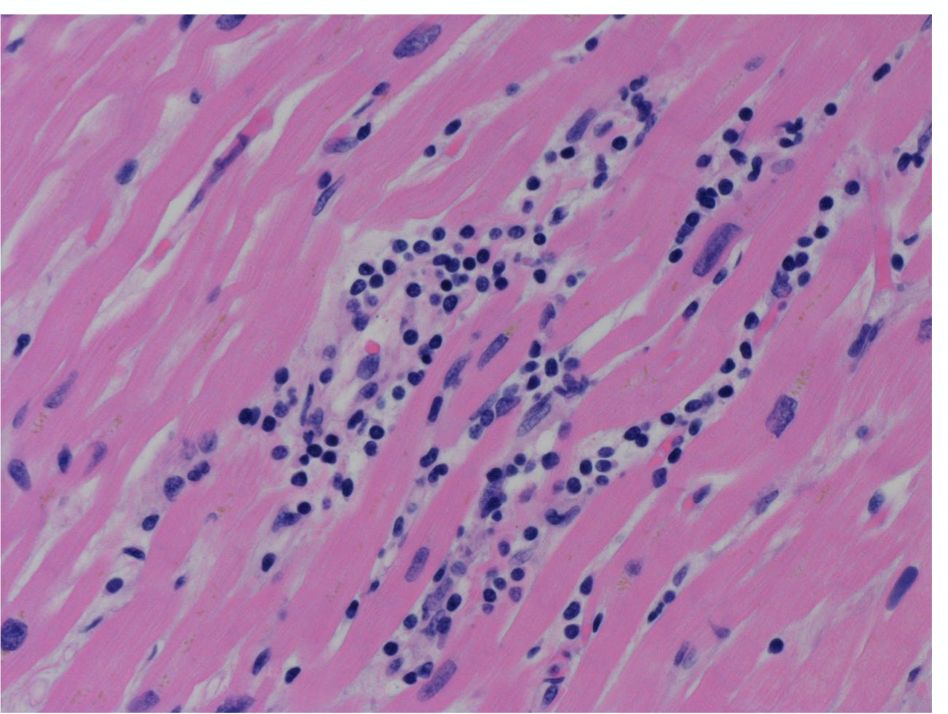

in lymphocyte myocarditis, you can see ___ ___. Outline some etiologies.

myocyte necrosis; clusters of lymphocytes in the myocardium.

Etiologies include: idiopathic, viral/post viral, autoimmune, drugs.